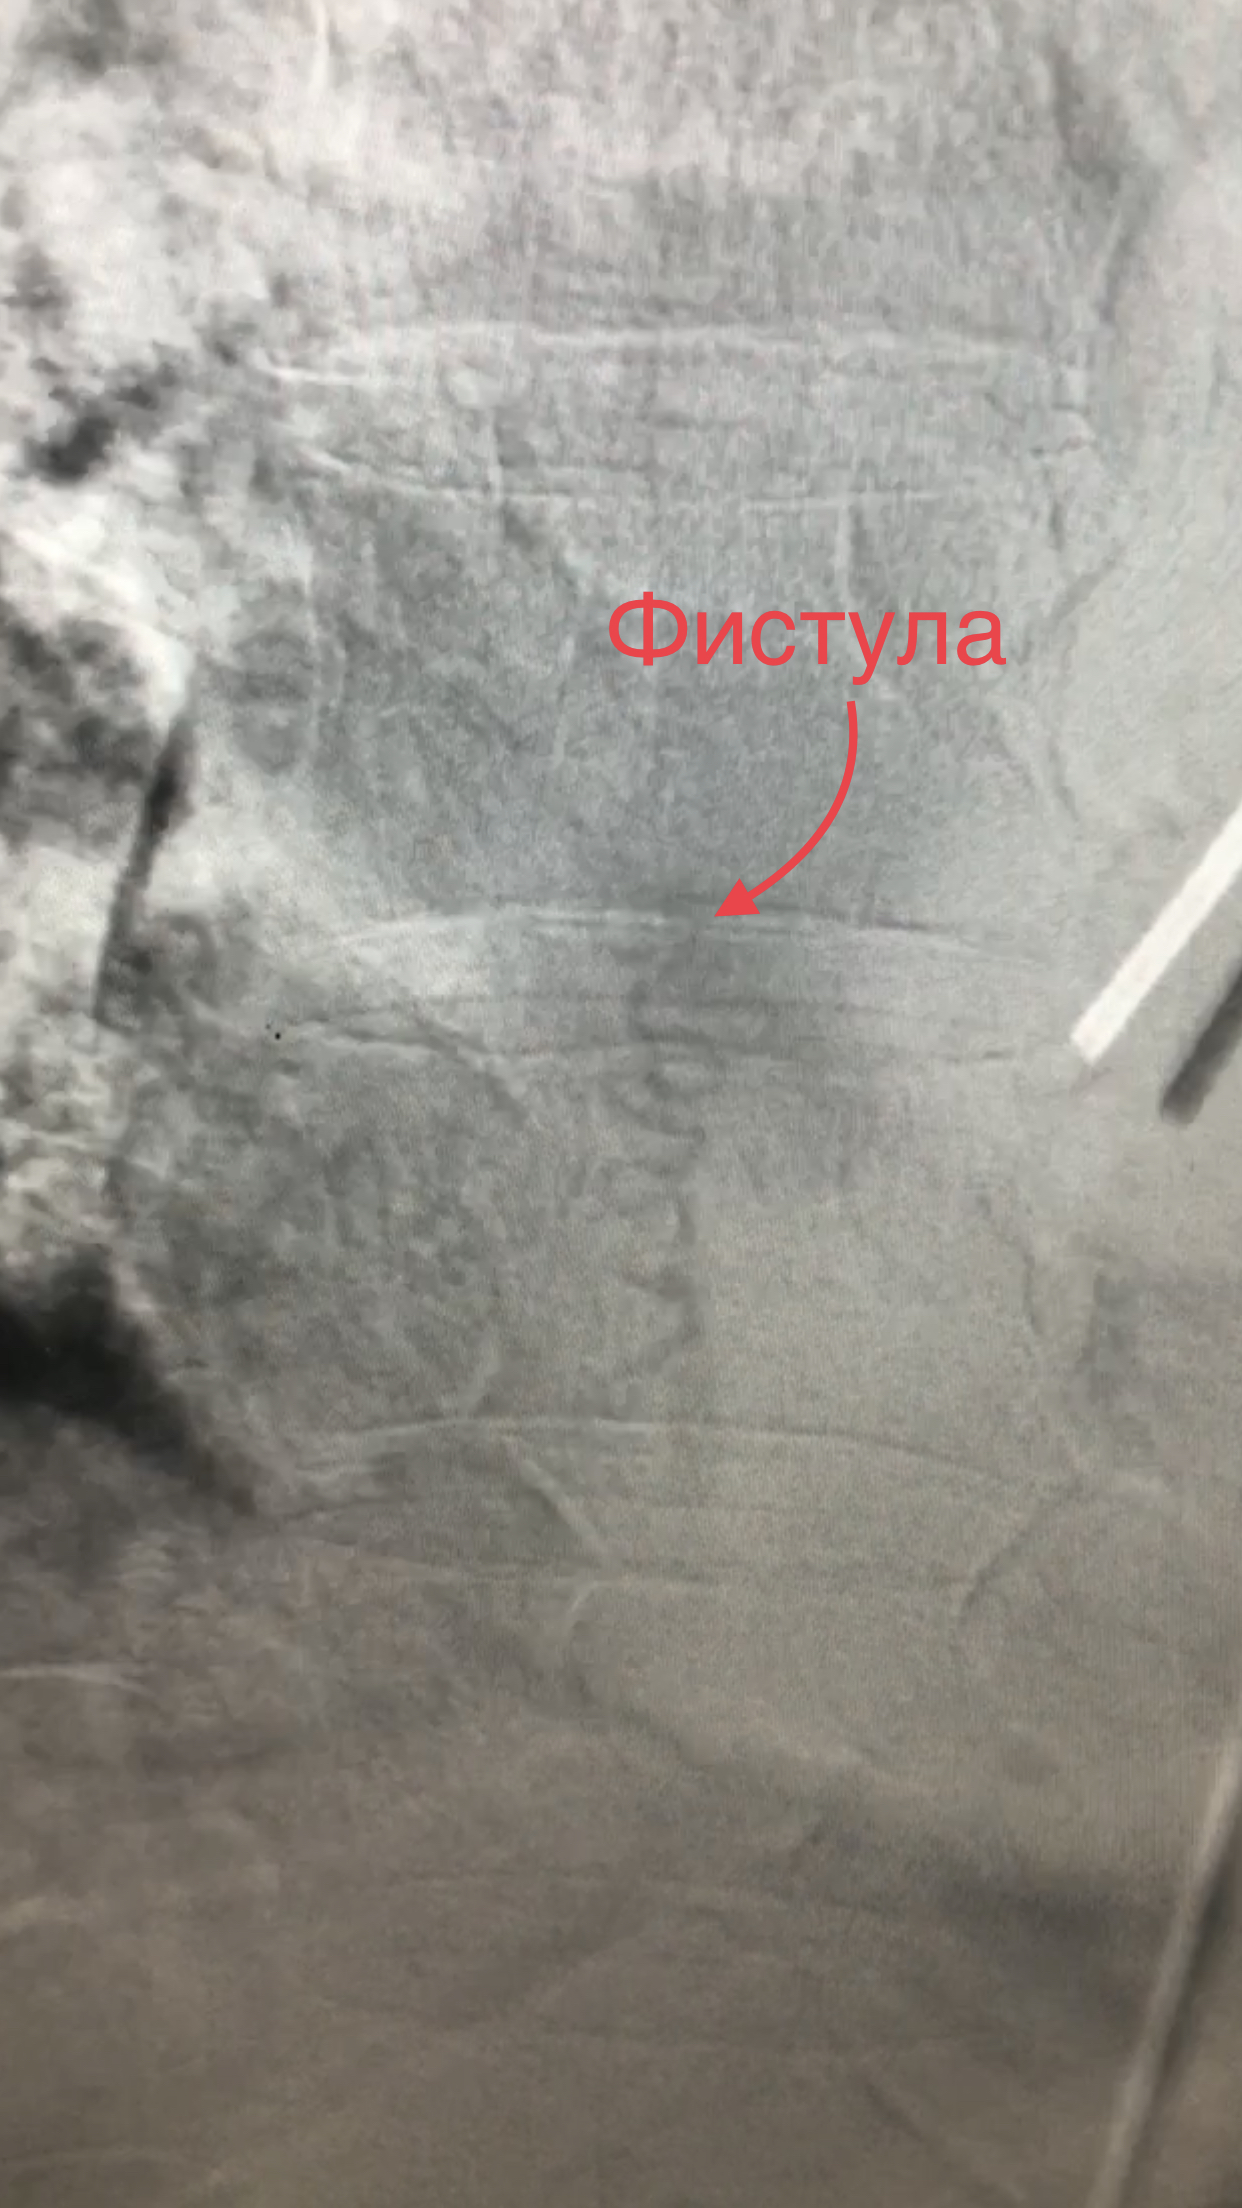

Для точной постановки диагноза в НМИЦ им. В. А. Алмазова д.м.н. Александр Викторович Савелло в гибридной операционной выполнил пациенту спинальную ангиографию (диагностическую операцию под местной анестезией, в ходе которой через бедренную артерию производится заход микрокатетером во все питающие спинной мозг сосуды и по распределению контраста ищется фистула).

После того как предположения врачей подтвердились, был сделан следующий этап — микрохирургическая операция. Под рентгеном медики определили точное расположение патологического сосуда. С целью контроля функций спинного мозга во время операции проводился нейрофизиологический мониторинг. Для этого пациенту установили специальные электроды, затем наложили временную клипсу на патологический сосуд и, убедившись в том, что он не участвует в нормальном кровоснабжении спинного мозга, пересекли его.